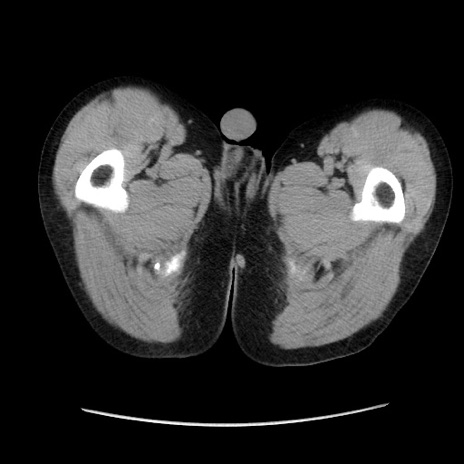

症例37(横断像)

【症例】40歳代 男性

【主訴】腹痛

【現病歴】4時間ほど前に電車に乗車中に臍部上より腹痛出現。徐々に増悪し起立困難となり、救急外来受診。生ものは数日食べていない。今朝お雑煮を食べた。

【身体所見】BT 36.8℃、BP 117/84mmHg、HR 91/min、SpO2 97%、苦悶様、腹部:臍上部広範囲圧痛あり、反跳痛±

【データ】WBC 8100、CRP 0.03